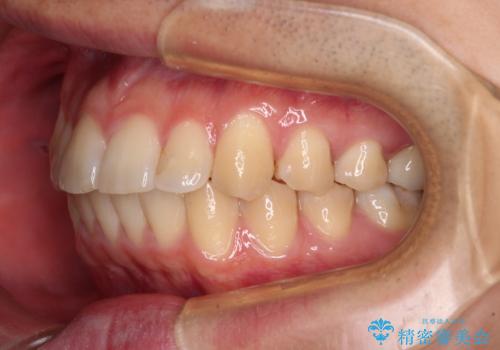

- 上下前歯のデコボコを気にして来院された患者様です。

マウスピース矯正でもワイヤー矯正でも対応可能でしたが、インビザラインによる自己管理が煩わしいとのことで、ワイヤー装置にて矯正治療を行うこととしました。

口元はやや突出感がありましたが抜歯矯正をするほどではないため、舌突出癖を改善するトレーニングをしっかりと行っていただき、現在よりも唇が閉じやすい位置に仕上げていくこととしました。